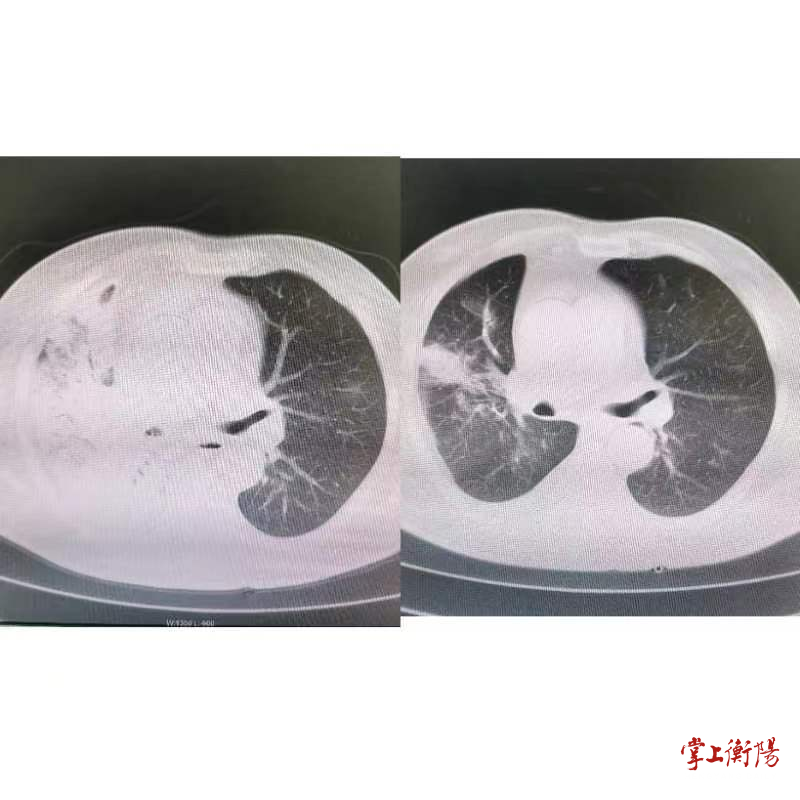

▲治疗前(左)和治疗后(右)肺部情况对比。

2022年12月29日,一位56岁重症新冠患者周某来到衡阳市第三人民医院新冠二区诊治,周某发热、咳嗽已持续一周,到医院的时候出现呼吸衰竭的症状,且患者存在脑梗死、糖尿病等基础疾病。经过检查,患者是因为新冠病毒感染引起的右肺感染,引起肺泡阻塞,右肺已经演变为“白肺”,吸氧状态下患者血氧饱和度仅有72%—82%,远低于98%的正常值,医院紧急为患者进行了抢救。新冠二区主任李芳、护士长黄英积极带领救治团队开展精准治疗,精心呵护,为其注射胰岛素降低患者血糖浓度,对患者进行了小剂量的激素抗炎,接着予以“奈玛特韦/利托那韦片”口服抗病毒、“泰能”抗感染,全程辅以经鼻高流量给氧及俯卧位通气改善肺通气及促排痰对症治疗。5天后,患者在吸氧状态下血氧饱和度已经上升到94%,1月5号,CT提示病灶明显吸收好转,“白肺”感染面积也在逐渐减少,再经过几日巩固治疗便可出院。